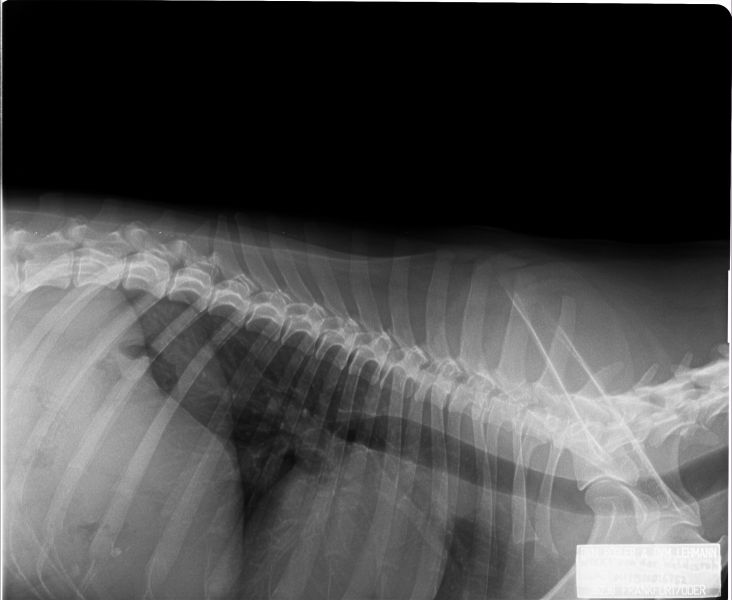

Auswertung der Röntgenbilder von Wikki  aus Augsburg:

HD- fast normal; ED-normal